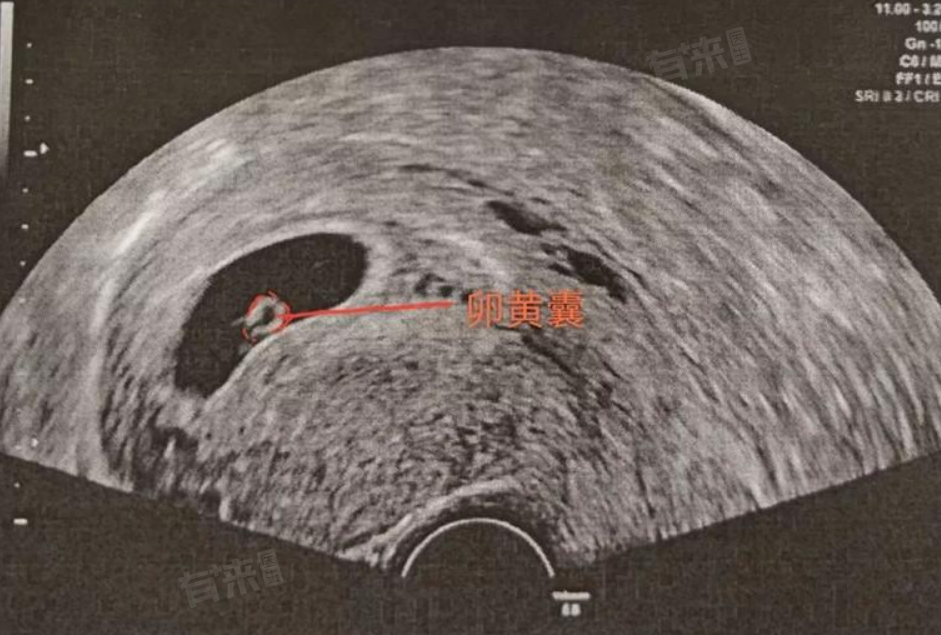

4、定期复查:按时参加所有预约的超声波和血液检测,监测囊胚发育情况及激素水平变化,确保及时发现并处理任何问题。